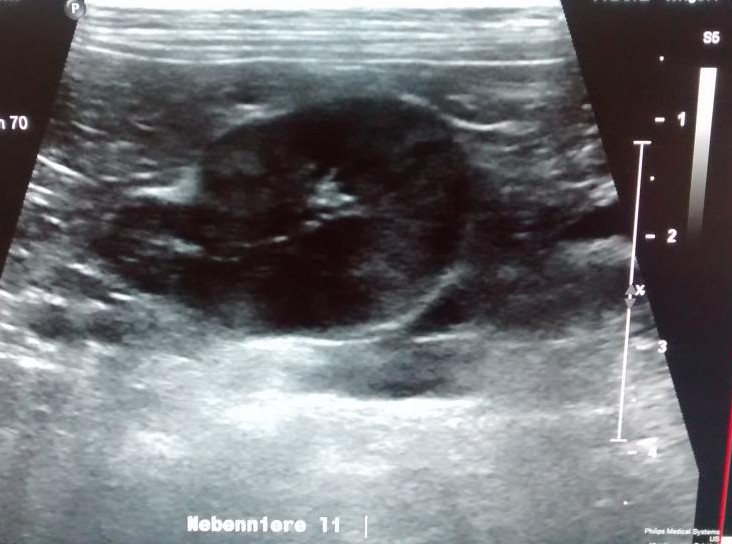

Erkrankungen der Nebennieren

Die Nebennieren sind kleine aber wichtige hormonproduzierende Organe neben den Nieren. Entgegen ihres Namens haben sie mit der harnproduzierenden Funktion der Nieren nichts zutun. Sie sind für die Produktion von Glukokortikoiden, Mineralokortikoiden und Geschlechtshormonen zuständig. Diese Hormone ermöglichen dem Körper eine adäquate Reaktion auf Streß und beeinflußen zahlreiche Stoffwechselfunktionen. Sowohl eine Unterfunktion (Addison) als auch eine Überfunktion (Cushing) führen beim Hund zu schweren körperlichen Einschränkungen.

Ältere Katzen leiden manchmal am sogenannten Coon-Syndrom, einem Nebennierentumor der zu Bluthochdruck und lebensgefährlichem Kaliumverlust führt.